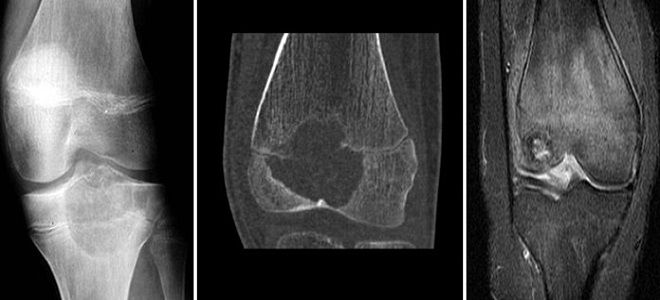

Рак костей – диагностика

Когда у пациента возникает подозрение на онкологическое заболевание костей, диагностика сосредоточена на быстром определении местоположения опухоли и ее размеров. Если анализы могут указать на наличие опухоли, то точное определение ее локализации, размеров и типа возможно только с применением современных аппаратных методов обследования.

По этой причине опытные онкологи при первых подозрениях на рак назначают компьютерную томографию или магнитно-резонансную томографию. Эти методы позволяют получить надежные данные о опухолевых процессах в костной ткани и подтвердить визуальные признаки рака костей. С их помощью также можно опровергнуть предварительный диагноз.

Рентген при раке костей

Рентгенография представляет собой один из ключевых методов для диагностики рака костей. С её помощью можно не только определить местоположение, но и характер изменений в структуре костной ткани. Среди важных рентгенологических признаков злокачественной опухоли, к которой относится остеома кости, специалисты выделяют следующие:

- наличие очага разрушения костной ткани;

- проявление периостальной реакции, визуально определяемой как характерный козырек;

- длинные нитеобразные спикулы, располагающиеся перпендикулярно кости;

- наличие мягкотканевого компонента с участками обызвествления.

МРТ при раке костей

После выявления воспалительного процесса специалисты назначают магнитно-резонансную томографию (МРТ) опухоли костей. Это обследование позволяет получить полное представление о структуре новообразования, его типе и размере. МРТ предоставляет исчерпывающую информацию, на основе которой врачи формируют план лечения и возможного хирургического вмешательства. Данное исследование может проводиться несколько раз для мониторинга эффективности химиотерапии и динамики лечения рака костей.